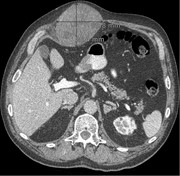

Chylous mesenteric cysts: a rare surgical challenge

Lorenzo Dioscoridi and others

Journal of Surgical Case Reports, Volume 2014, Issue 3, March 2014, rju012, https://doi.org/10.1093/jscr/rju012